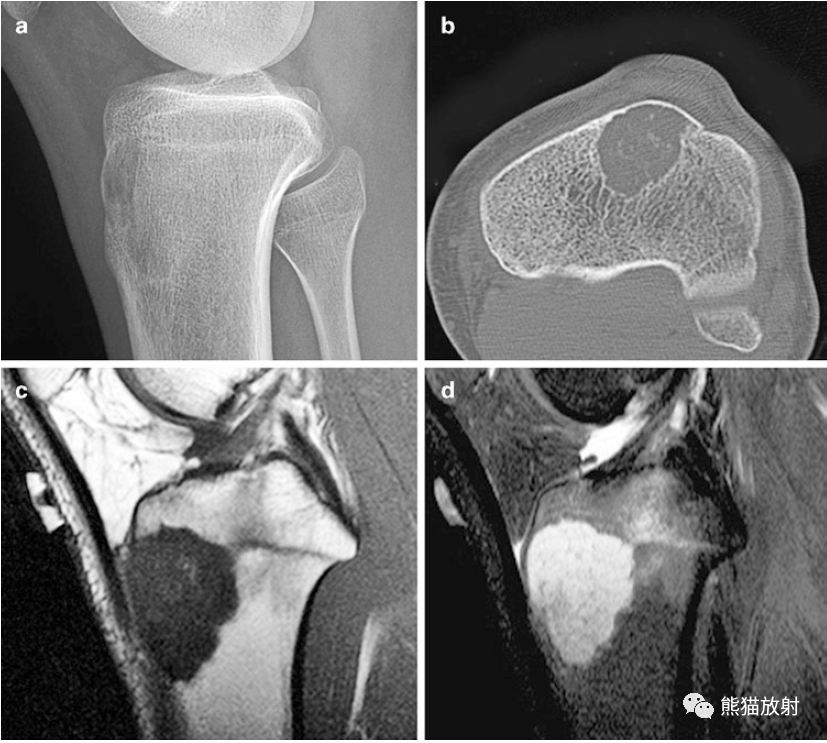

丁香园论坛>影像核医学>帖子详情>上图所示:右股骨远端软骨母细胞瘤右